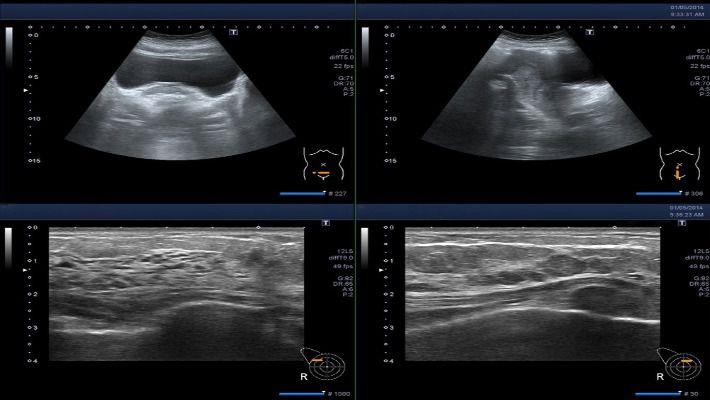

אי פריון מכאני הוא מצב בו קיימת בעיה במבנה הרחם ו/ או החצוצרות הגורמת לקושי בכניסה להריון. כדי לאבחן בעיה זו, נשים רבות נשלחות לביצוע צילום רחם – בדיקה הכרוכה בכאב ואי נוחות ומערבת סכנת קרינה. בדיקת סונוהיסטרוסלפינגוגרפיה היא חלופה חדשנית המאפשרת לאבחן את בעיית אי הפריון המכאני ללא כל אי נוחות או סכנה. היא כוללת הדמיה של הרחם והחצוצרות בסונר דו ממדי ותלת ממדי, תוך הזלפה של מים פיזיולוגיים לחלל הרחם העוברים גם דרך החצוצרות

בדיקת סונוהיסטרוסלפינגוגרפיה נחשבת כיום כבדיקת הבחירה הראשונה והמועדפת לאבחון בעיות אי פריון על רקע מכאני. למעשה, מדובר בבדיקת אולטרה סאונד פשוטה המשמשת להדמיית חלל הרחם והחצוצרות. באמצעותה ניתן לבחון את תקינות מבנה הרחם, חלל הרחם והחצוצרות, כדי לוודא שלא קיימת כל חסימה אשר עלולה למנוע כניסה להריון. בניגוד לבדיקת צילום הרחם, בדיקה זו אינה דורשת תפיסה של צוואר הרחם, שימוש בחומר ניגוד (במהלך הבדיקה מוזלפים מים בלבד) וחשיפה לקרינה. על כן, היא נחשבת בטוחה יותר ופחות כואבת מצילום רחם .

במהלך הבדיקה מוזלפת תמיסת מים פיזיולוגיים (סליין) אל תוך הרחם והחצוצרות. בדיקת האולטרה סאונד משמשת כדי להדגים את מעבר הנוזל דרך החצוצרות בזמן אמת ובכדי לבחון את מידת הפתיחה שלהן לשם מעבר נוזלים באופן חופשי וכדי לבחון קיום של ממצאים, כמו פוליפ, שרירן הידבקויות בו. בדיקת הסונוהיסטרוסלפינגוגרפיה אורכת כ-15-10 דקות. לאחר הבדיקה יתכנו תחושת אי נוחות או כאבים הדומים לאלה המורגשים בזמן הוסת החודשית באזור האגן ובבטן. הכאבים נובעים מהתכווצות הרחם. תחושות אלה יחלפו לרוב תוך זמן קצר לאחר הבדיקה. במקרים מסוימים יכול להופיע דימום קל לאחר הבדיקה שמקורו לרוב בצוואר הרחם.

במרכז מור לאישה, בדיקת הסונוהיסטרוסלפינגוגרפיה מתבצעת על ידי שני רופאים מומחים מתחום הפריון והאולטרה סאונד, תוך שימוש במכשיר הדמיה מתקדם המאפשר שימוש בטכנולוגיות תלת וארבע ממדיות.